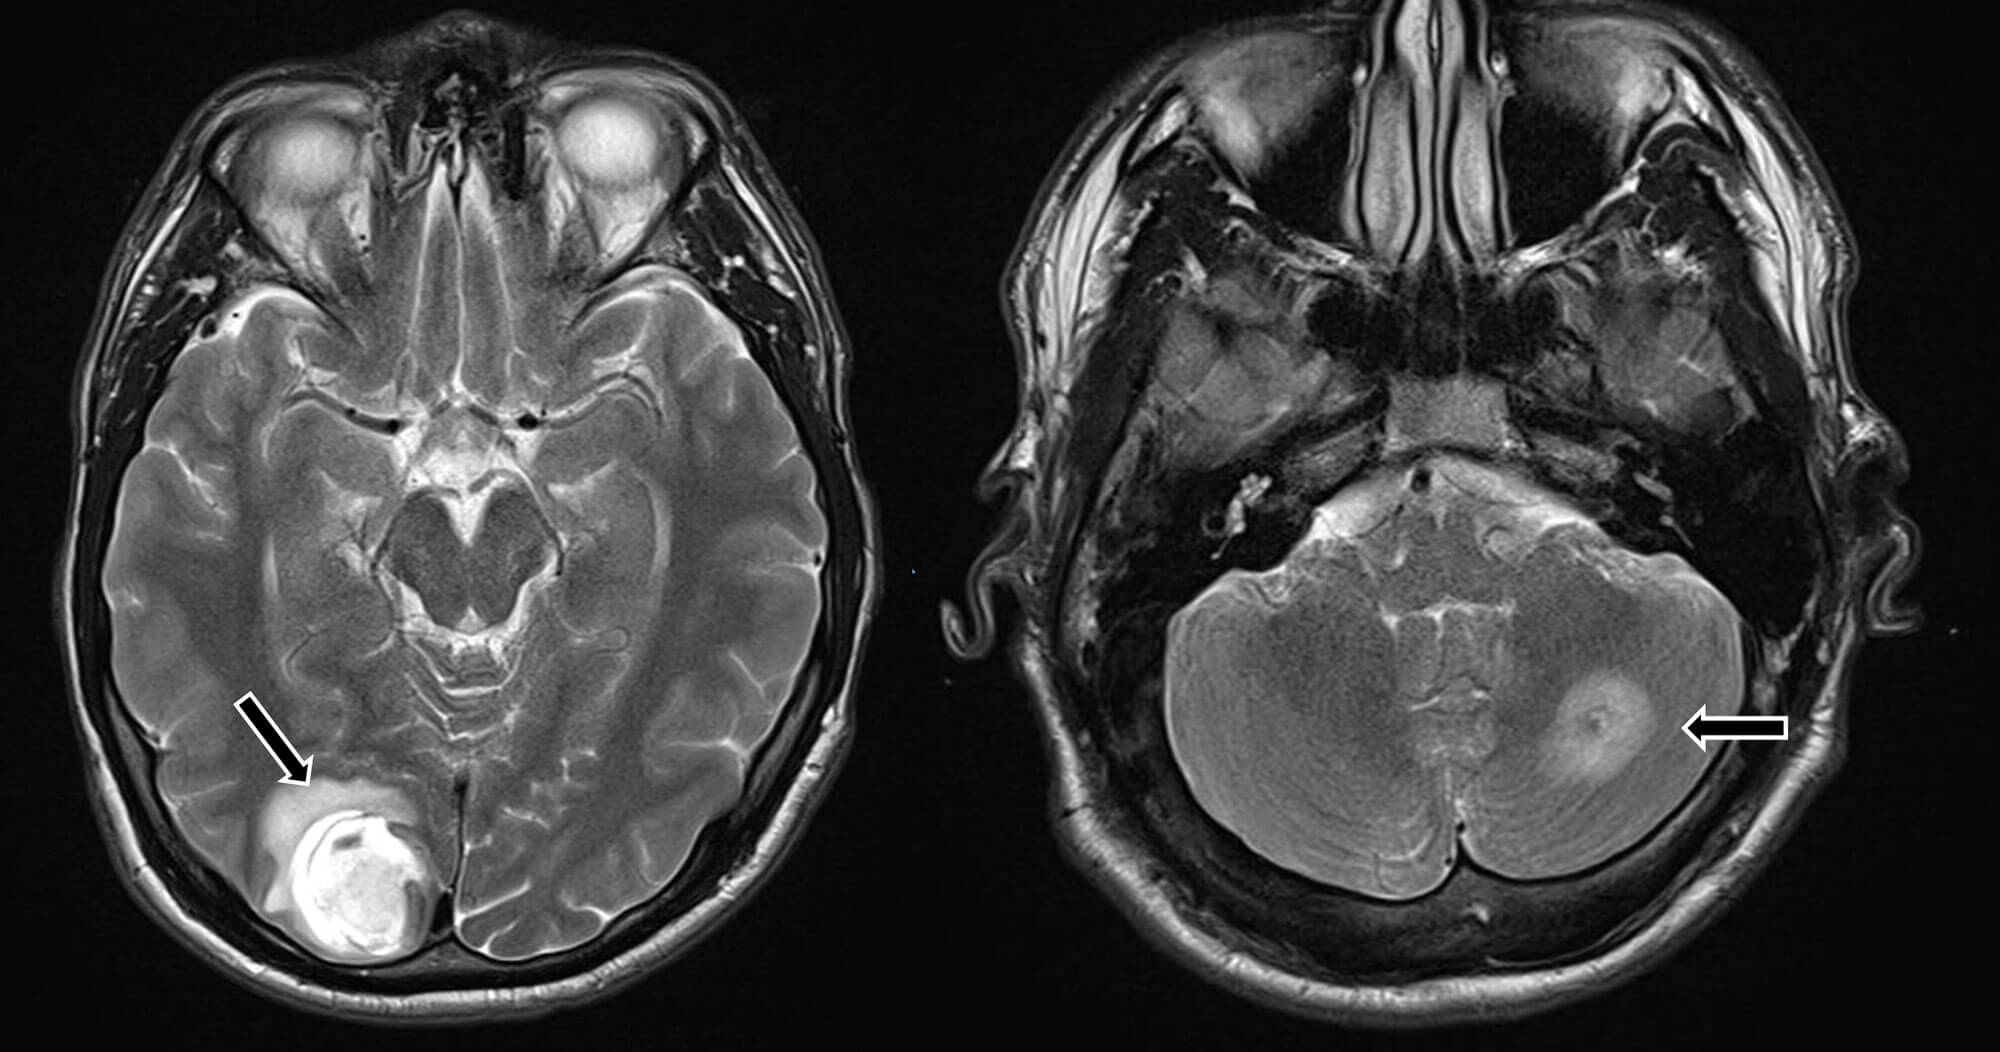

On examination, the right testicle was globally irregular, with the left atrophic and difficult to examine. US of the testes showed a grossly abnormal right testicle, measuring 92 x 53 x 60mm, and two small lesions with vascularity in the upper pole of the left testis concerning for malignancy (Figure 3).

Figure 3: Two abnormal areas on the left atrophic testis arrowed (L) and grossly abnormal right testicle (R).